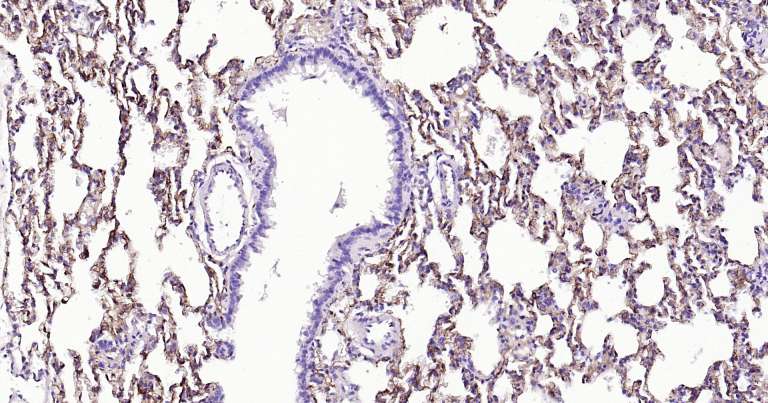

Immunohistochemical analysis of paraffin embedded rat lung tissue slide using IHC0175R (Rat Tau-4 IHC Kit).